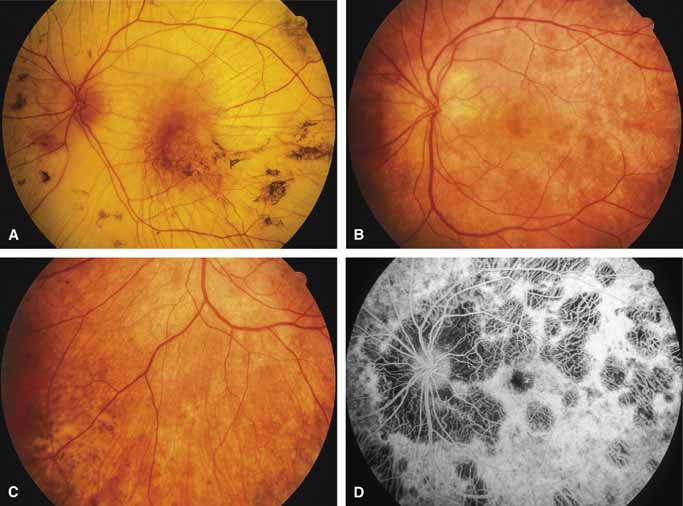

First described by Nettleship12 in 1884, central areolar choroidal dystrophy (CACD) (MIM No. 215500, Phenotype catalog number (MIM) from McKusick VA: Mendelian Inheritance in Man. Catalogs of Human Genes and Genetic Disorders. 12th ed. Baltimore: Johns Hopkins University Press, 1998 [http://www.ncbi.nlm.nih.gov/Omim/]), as it is most appropriately called,13 has been described under many names, including central areolar choroidal sclerosis, central areolar choroidal atrophy, central angiosclerosis, and central senile choroiditis.14,15 The disorder can be autosomal dominant or autosomal recessive, and phenocopies can occur from many other diseases, including mutations of peripherin/RDS16–19 and advanced stages of macular dystrophies (see later text). A locus for CACD has been identified on chromosome 17p.20 The earliest symptoms result from pericentral scotomas and include difficulty reading, poor dark adaptation, reduced visual acuity, and glare sensitivity. The earliest fundus findings are subtle and include pigment epithelial and choriocapillaris lesions in the macula (Fig. 1A) that enlarge and eventually form the punched-out central atrophic lesions typical of this disease (Fig. 1B). Histopathology shows fibrotic scarring with absence of choriocapillaris, retinal pigment epithelium, and overlying photoreceptors in the affected areas.21 The Ganzfeld electroretinogram is usually normal early in the course but may become mildly to moderately abnormal for cone and rod responses late in the course of disease when extensive atrophy of the choroid and secondarily the pigment epithelium and neurosensory retina occurs. Recent studies using the multifocal ERG have indicated that the abnormality of retinal function extends beyond the borders of the visible atrophy and is consistent with presynaptic photoreceptor dysfunction.22 The EOG can be normal or mildly abnormal depending on the extent of associated retinal pigment epithelial dysfunction.

Other forms of central choroidal dystrophy exist that do not show the discrete oval lesions of typical central areolar choroidal sclerosis. These forms of central choroidal choriocapillaris atrophy often present with progressive pigment epithelial mottling and patchy choriocapillaris atrophy initially limited to the macula (Figs. 2A and 2B). With time, the atrophy enlarges and eventually encompasses the entire posterior pole (Fig. 2C). For this form of central choroidal atrophy, a gradual transition usually occurs from atrophic central pigment epithelium and choriocapillaris to essentially normal retina and choroid in the peripheral fundus.

Bietti's crystalline dystrophy (MIM No. 210370) of the cornea and retina is an autosomal recessive disorder that is characterized by the presence of crystals of unknown composition in the stroma of the peripheral cornea and at several layers of the retina (Figs. 3A and 3B).23 The disease can be subdivided into regional and diffuse forms, and the lack of any reports of the two patterns in the same family suggests genetic heterogeneity and not just variable expressivity.24,25 The regional form begins in midlife as pericentral scotomas that cause difficulty reading and reduced central visual acuity. Peripheral retinal function is retained and the electroretinogram and electrooculogram are normal or near normal even in moderately advanced disease. The fundus appearance and fluorescein angiogram reveal regional loss of pigment epithelium and choriocapillaris limited to the posterior pole (Figs. 3C and 3D). The finding of abnormal crystals in leukocytes indicates that this is a systemic metabolic disorder.24